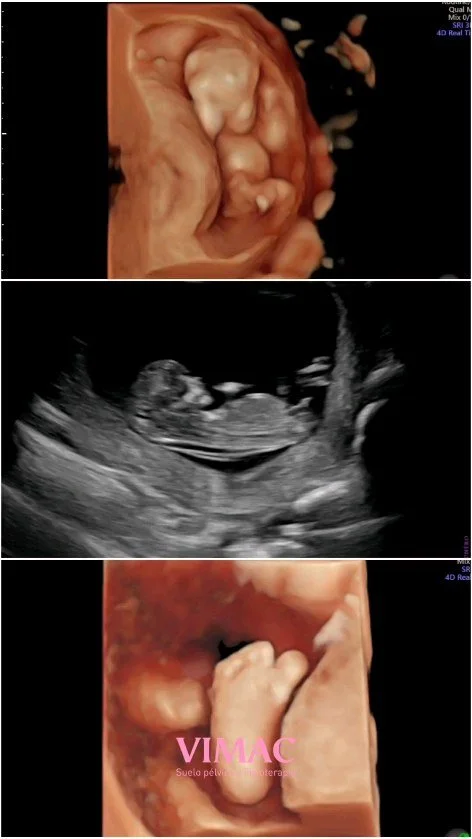

Suelo Pélvico & Fisioterapia

Daremos flexibilidad al periné evitando posible desgarro y episiotomía.

Recuperación posparto

Favorecemos la disminución del útero y todos sus ligamentos, trabajaremos diástasis abdominal y cicatriz de la cesárea, episotomía o desgarro.